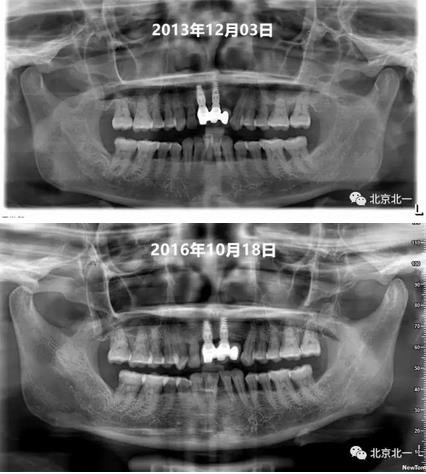

圖十、圖十一:2013年到2016年比較X片,骨平面很穩(wěn)定。牙齦及牙周黏膜健康,區(qū)別在于2016年時候31牙位缺失。